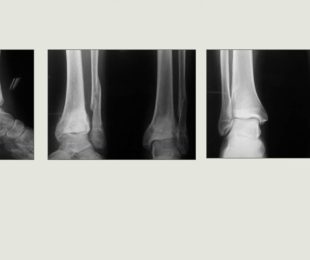

13 -Hemimelia Fibula